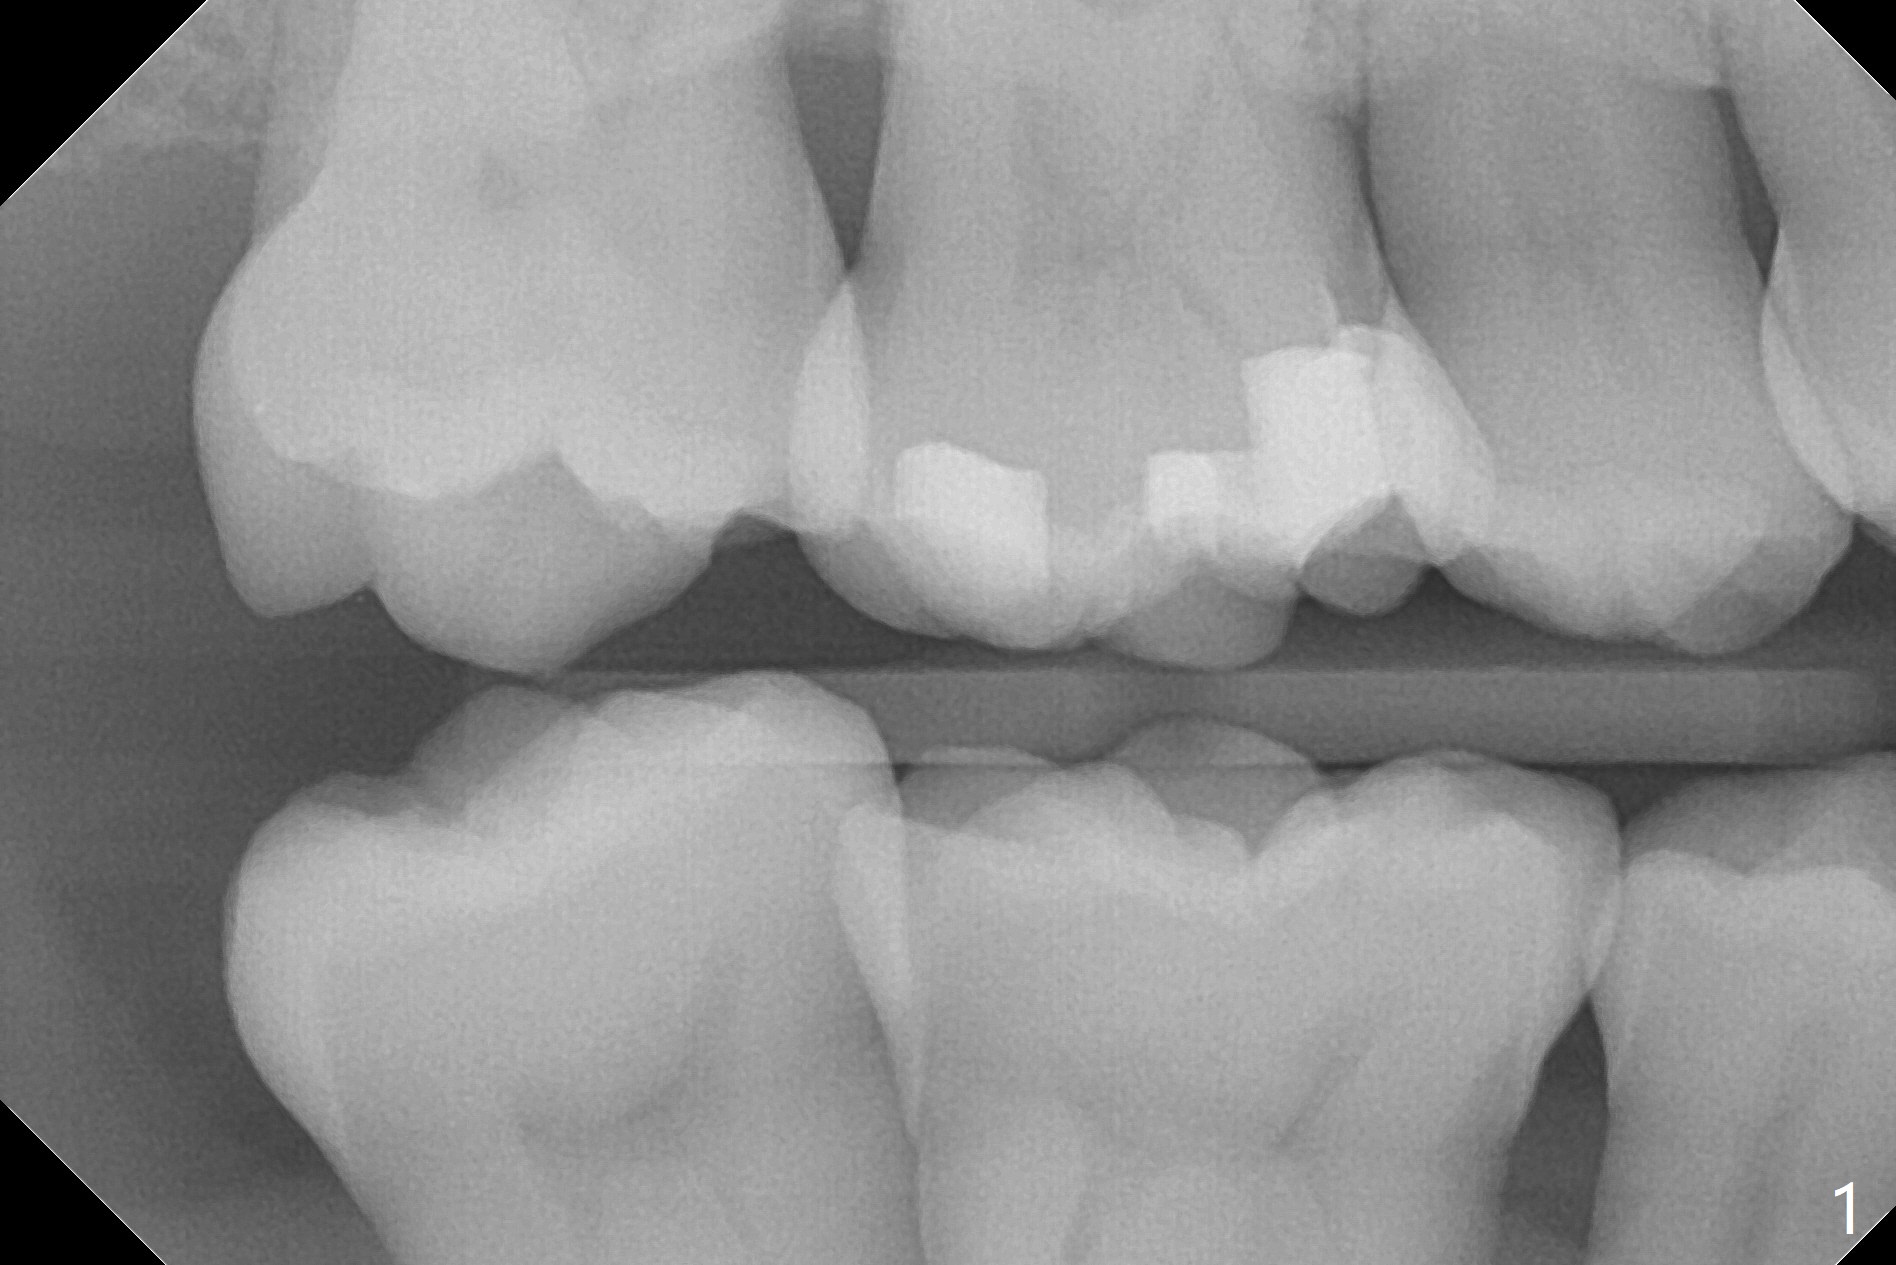

A 47-year-old man, a possible bruxer (Fig.1), is concerned about the mobile 2nd molar and lower central incisor (Fig.2,3). To prevent periimplantitis, a 2 mm 1-piece implant and a short one (5x5 mm) will be placed subcrestal at these sites, respectively (Fig.4,5). Sticky bone is a must. Pulpal test will determine whether RCT is required for #30 (Fig.5 curved white line). In fact the tooth #30 is tested to be vital. Onlay graft is an option for #31 (Fig.6 red rectangle). There is history of #32 extraction. The severely periodontally affected tooth #25 (Fig.7 *) has narrow mesiodistal space (Fig.8). It is the best treated with extraction with bone graft and self drifting.